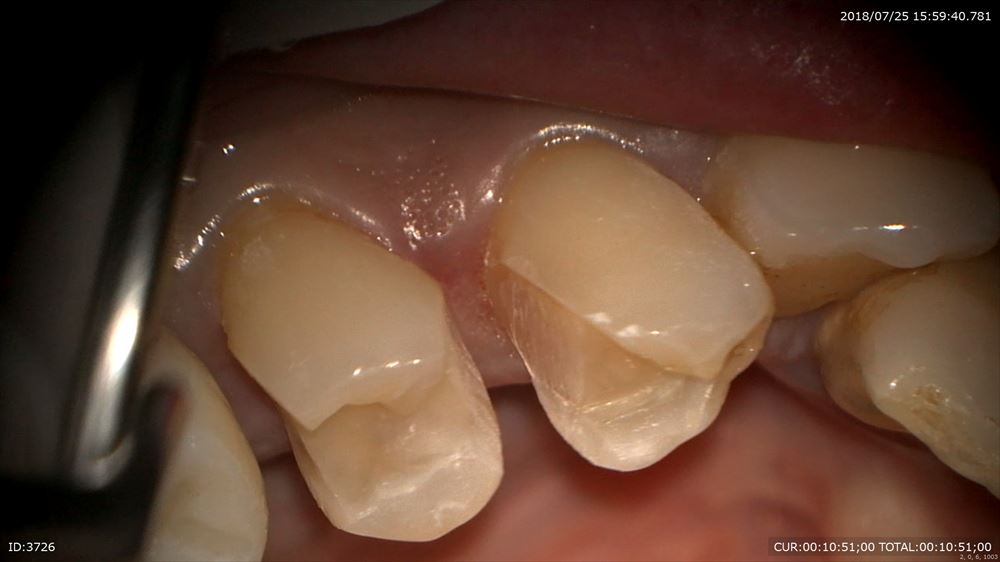

マイクロスコープを使用し無痛で除去

MTAセメントで神経を保護

ここまでで前回は終了。予後を数週見ます。

問題ないので精密な型とり。ここもマイクロスコープを使用。

活性材

シリコン

気泡をいれない

マイクロスコープを使用することでこのように形成もスムーズに歯茎を傷めず治療が可能です。